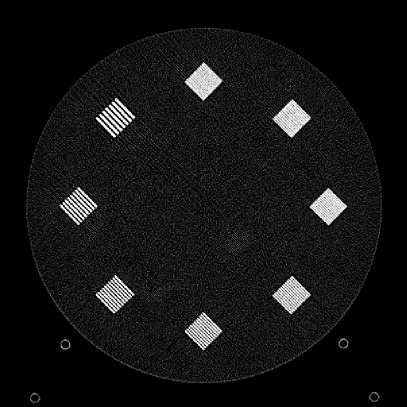

To evaluate image quality, we first tested the performance of JENG on a standard CT phantom, CT ACR 464 phantom 35. Then we tested JENG on 5 clinical thoracic datasets and 3 abdominal datasets. The ACR 464 phantom contains four modules in total, with each module 40 mm in depth and 200 mm in diameter. The first module has 4 different inserts to test CT number fidelity. In addition, the module contains a series of wires for cross-plane resolution evaluation, shown as white horizontal bars near the center in Fig. 9(a), and are visible in 0.5 mm z-axis increments. The second module tests low contrast resolution, but is not used in this paper. The third module, shown in Fig. 9(b), is a uniform cylinder of water-equivalent material of 0 Hounsfield units (HU), and we used this module to quantitatively measure image noise profile and in-plane resolution. The fourth module consists of resolution bars of various spatial frequencies for analysis on high contrast resolution. To scan the phantom, the scanner setup used dual sources with 2 focal spots at each source. In addition, the projections were acquired using the same protocol for clinical thoracic scans with 100 KV, a nominal tube current of 718 mA and a high helical pitch of 2.8. For all experiments, we compared JENG against the state-of-the-art Siemens ADMIRE, reconstructed with a BL-64 soft tissue sharp kernel, and we define ADMIRE as the clinical standard hybrid IR method for the rest of the paper.

Figure 10: Clinical Standard hybrid IR vs JENG performance, with a display window center of 650 HU and a window width of 1500 HU. The spatial frequencies for bar patterns from top going clock-wise are 1.2, 1.0, 0.9, 0.8, 0.7, 0.6, 0.5, 0.4 mm-1. (a) The clinical Standard hybrid IR at L1 denoising strength using a soft tissue high contrast kernel. Note that significant aliasing streaking artifacts are present near the bar patterns. (b) JENG at a comparable L1 noise level but with much clearer bar pattern and fewer artifacts than the clinical standard hybrid IR. (c) The clinical standard hybrid IR at a stronger denoising strength of L3. (d) JENG at a comparable L3 noise level.

The first experiment we performed was a visual comparison of in-plane spatial resolution between JENG and the clinical standard hybrid IR. We used the ACR phantom module 4 for this evaluation, which has 8 resolution bars of various spatial frequencies from 0.4 mm-1 to 1.2 mm-1. To obtain a fair comparison, we matched the image noise variance in the uniform regions of JENG and the clinical standard hybrid IR and studied their in-plane spatial resolution and undersampling streaking artifacts. In addition, we performed two sets of experiments. The first set of experiments matched their image noise variance at the L1 denoising strength of the clinical standard method with a noise variance of 33926 in the uniform regions. The second set of experiments matched their image noise variance at stronger L3 denoising strength of the clinical standard method with a noise variance of 12988 in the uniform regions.

Fig. 10 is an example image for resolution bars and the spatial frequencies for the bar patterns from top going clockwise are 1.2, 1.0, 0.9, 0.8, 0.7, 0.6, 0.5 and 0.4 mm-1. Fig. 10(a) is the resolution bars reconstructed by the clinical standard hybrid IR at L1 denoising strength. Fig. 10(b) is JENG reconstructed at an image noise variance comparable to the L1 denoising. Fig. 10(c) is the clinical standard hybrid IR at a stronger L3 denoising strength and we can observe that the result at L3 denoising leads to less image noise than the result at L1 denoising in Fig. 10(a). Fig. 10(d) is JENG at an image noise variance comparable to the L3 denoising. To help readers better see the image quality difference between the clinical standard hybrid IR and JENG, Fig. 11 is the difference image between the two algorithms at L1 denoising. A noticeable difference between the clinical standard hybrid IR and JENG is that the clinical standard method in Figs. 10(a) and (c) have strong undersampling aliasing artifacts near the phantom periphery, which show a pattern of high density streakings and the streakings point along the direction of X-rays. In addition, the magnified sub-figures show that the bar pattern at 0.8 cycles/mm is unresolved with blurry details. In contrast, JENG in Figs. 10(b) and (d) effectively decimates the undersampling artifacts and the bar pattern in the magnified sub-figures of JENG is completely resolved with clearer details.